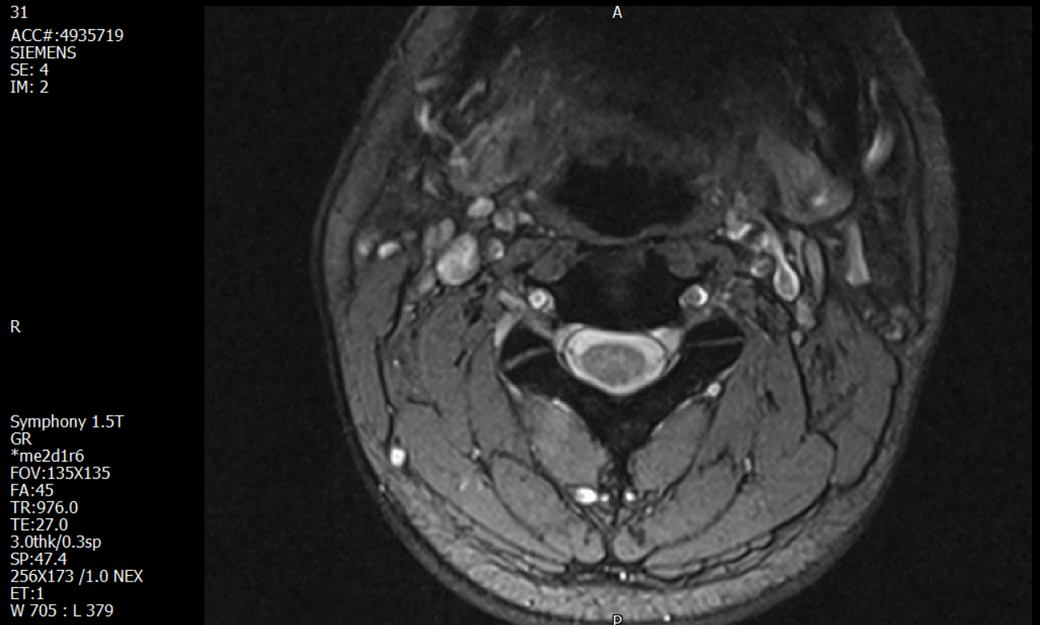

경추 요추 디스크 MRI판독 부탁드립니다.

- 3개월전 좌측 상지 저림(힘빠짐) 발생. 이틀뒤 에 좌측 하지 저림(힘빠짐) 발생.

-11월, 증상발생 직후 잠실소재 척추전문병원 MRI 요추경추 촬영 후 신경외과 박사 진료, 허리는 매우 건강, 경추는 퇴행성 진행되고 있지만 디스크라고 보기 어려움. 신경막만 살짝 건드리는 정도고 이 정도로 힘빠짐이나 저림이 오지 않고 원인은 다른 곳에 있을 가능성.

-올해 1월, 분당서울대병원 신경과 진료, MRI영상보더니 디스크가 있고 저림과 힘빠짐이 이에 기인했을 가능성이 충분히 있다고함. (경추만 말한것인지 요추도 포함인지 모르겠으나 디스크 시술 방안을 제시함) , 팔다리가 우연이 동시에 저림이 올수 있는지에 대해서 물었더니 이틀 상간으로 발생했기 때문에 동시라고 보기 어렵다고함...

1. MRI 상 , 경추와 요추에 디스크가 있나요? 있다면 좌측 팔과 다리에 저림 및 힘빠짐을 줄 정도인가요?

3. 디스크로 인한 증상이라면, 목과 허리의 디스크가 이틀 상간으로 문제가 생길수 있나요?

• 1. MRI 사진을 보았을 때 디스크를 의심해볼 수 있는 소견이 살짝살짝 보이긴 합니다만, 상하지의 저림 및 힘빠짐을 유발할 정도인지는 솔직히 회의적입니다.

3. 개인적으로는 디스크로 인한 증상이 아닐 것으로 보나, 만약 디스크가 맞다면 우연하게 목과 허리 디스크 발병이 이틀 간격을 두고 나타났을 가능성을 생각해야 하는데, 현실적으로 그 가능성이 높지 않습니다.

상기 MRI 소견으로는 심한 증상을 보일 정도는 아니며 디스크의 가능성은 적어보입니다.